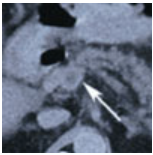

Mesenteric Venous Thrombosis

Sumeeta Mazzarolo, MD; Jose Lezama, MD; Kevin O'Brien, MD

A 63-year-old man with a history of hypertension and gastroesophageal reflux disease presented with progressive, sharp mid-abdominal pain.